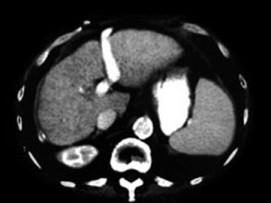

下列图像最佳诊断是什么 ( )A.肝囊肿B.肝脓肿C.肝硬化D.原发性肝癌E.肝包虫病

问题 下列图像最佳诊断是什么 ( )

选项 A.肝囊肿 B.肝脓肿 C.肝硬化 D.原发性肝癌 E.肝包虫病

答案 C